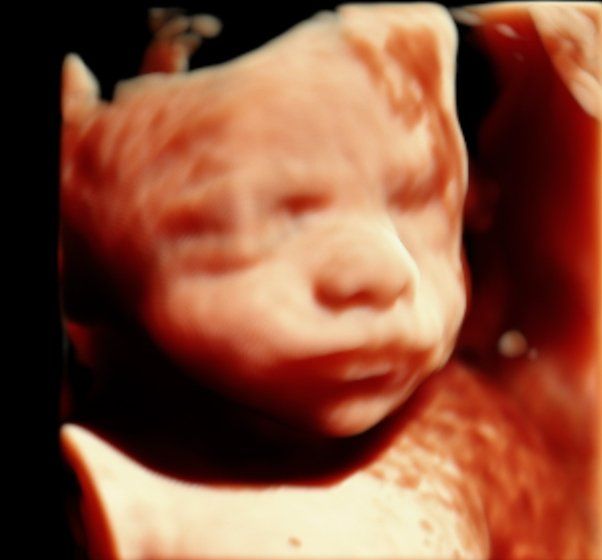

Desde 2016, año en que iniciamos nuestra andadura, nos hemos consolidado como

centro de referencia en Ecografía 5D de la provincia de Barcelona, siendo la opción

más recomendada por los profesionales y especialistas en ginecología

de la zona.

En la actualidad nos centramos en mantener el

liderazgo

en el sector a costa de ofrecer servicios de la máxima calidad, realizados por especialistas, y estar a la vanguardia en

tecnología y las novedades del sector.

En Centre Miramed trabajamos como servicio sanitario, con personal preparado para detectar posibles incidencias durante la exploración. Eso significa que, además de llevarte una experiencia única y unas imágenes inolvidables, también cuentas con la tranquilidad de que hay un criterio profesional detrás.

Porque no todos los centros son iguales, y en un momento tan importante, elegir bien marca la diferencia.